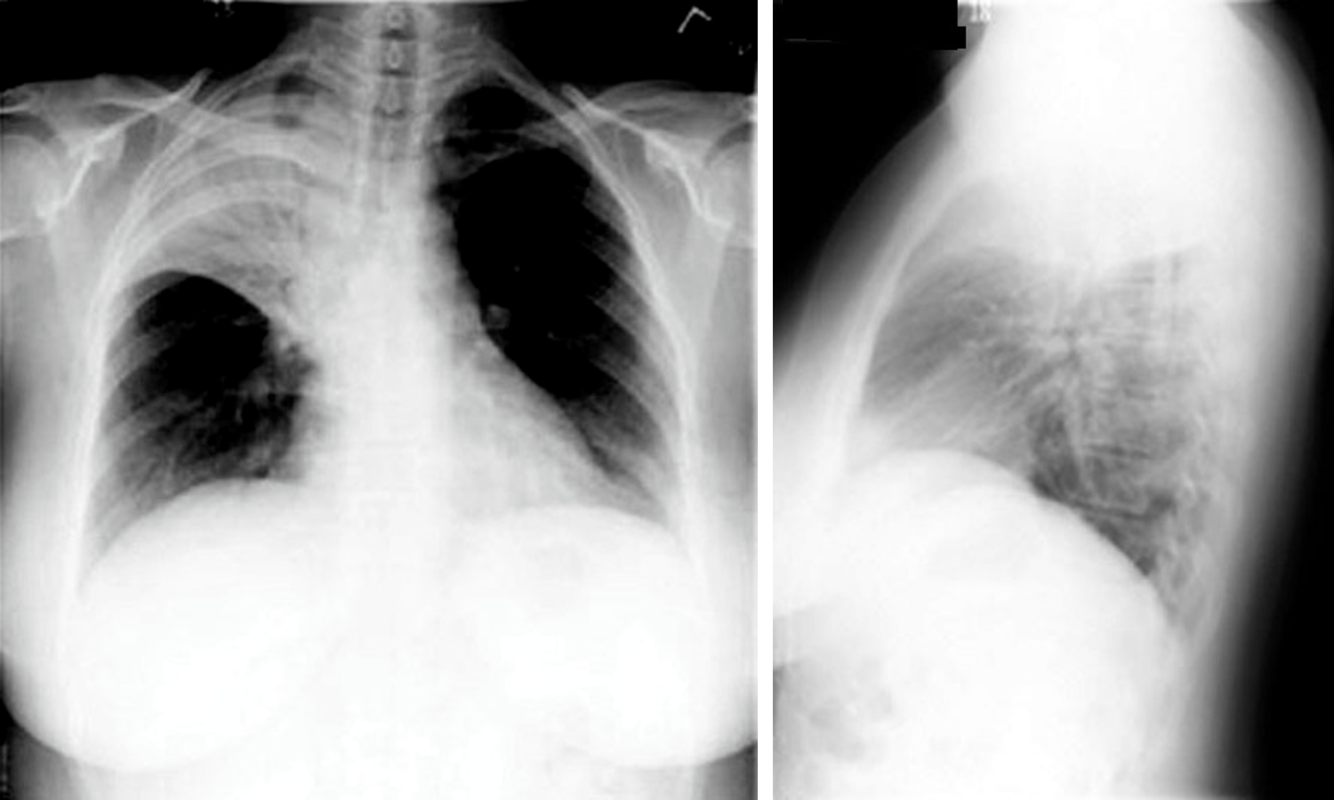

60yo female with history of congestive heart failure presents to the clinic with a 3 week history of worsening SOB

View

DX

DX: pleura effusion